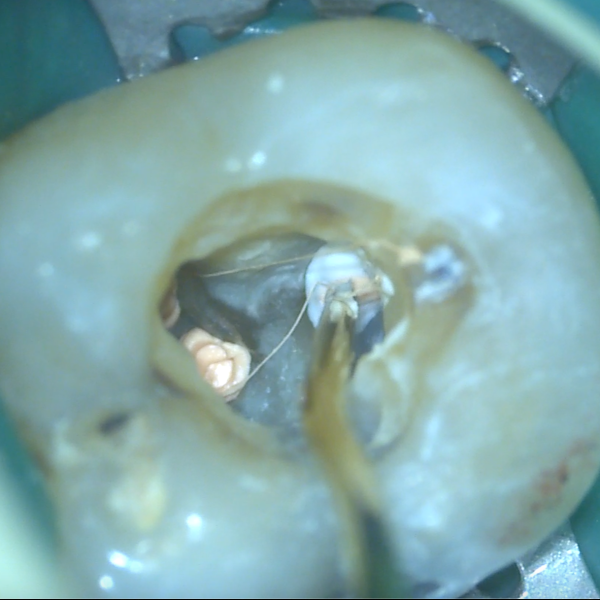

V určitých případech může být výhodná pístová technika. V rámci přednášky se dozvíte základní informace o kalcium silikátových materiálech – kdy je vhodné je využít, o kalcium silikátových sealerech – jaké existují, a také praktické informace o pístové technice – jak a kdy ji provést, jak si zjednodušit život a jak se vyhnout komplikacím.

Shrnutí kalcium silikátových sealerů a potřebného vybavení pro rychlé a efektivní zaplnění kořenových kanálků pomocí pístové techniky:

• Jaké sealery jsou vhodné?

• Hrají roli kanyly?

• Z čeho může být zhotoven píst?

• Jak moc tlačit?

• Jak velké je riziko extruze materiálu a kdy není pístová technika vhodná?